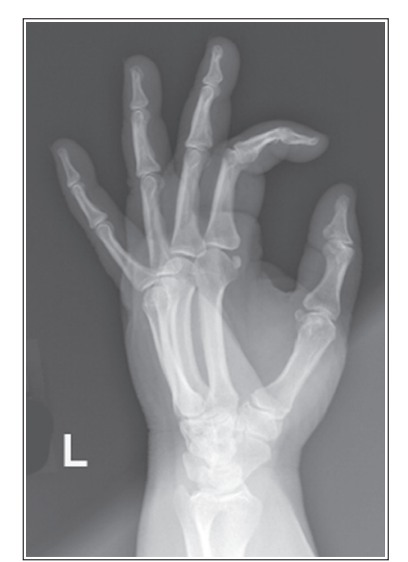

What is wrong with this oblique hand?

Unequal concavity between phalanges and MCs

Hand was slightly externally rotated